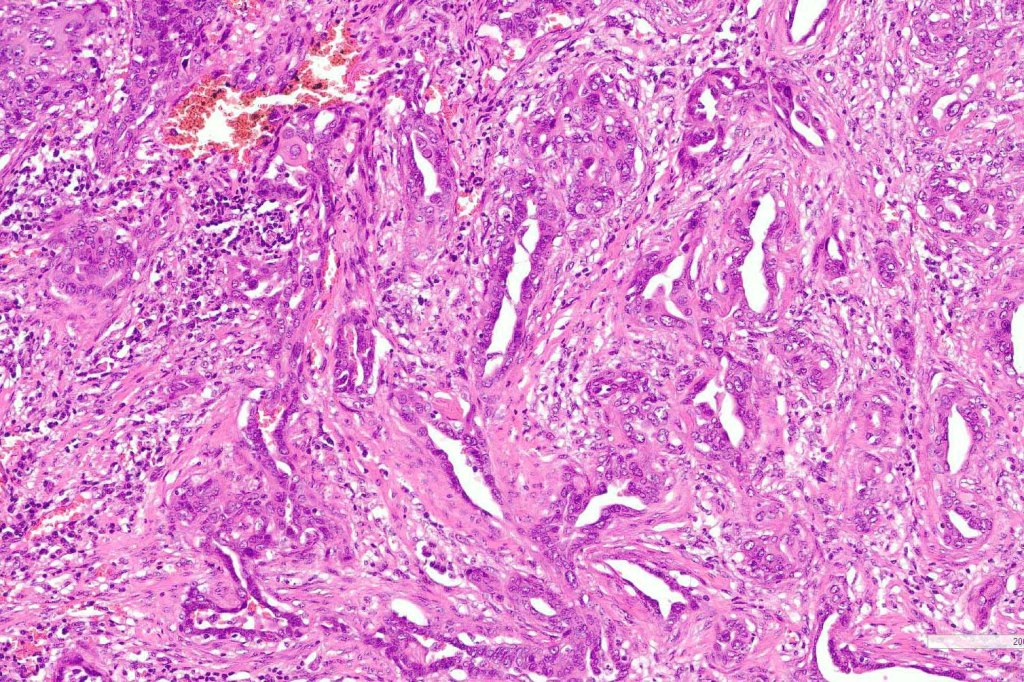

Histological features

- Solid narrow epithelial strands (sometimes predominates and keratocysts absent (eccrine epithelioma, syringoid eccrine carcinoma)

- Minimal pleomorphism

- Mitoses very sparse or absent

- Ductal differentiation

- Invariable perineural infiltration*

- Dense fibrous stroma